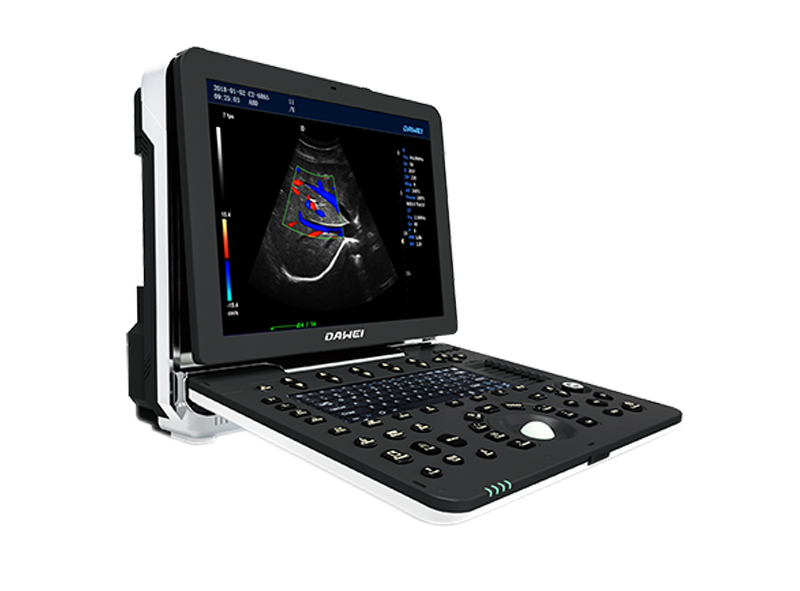

P5-VET便攜手提式獸用彩超機(jī)

全數(shù)字彩色動(dòng)物超聲診斷儀

彩色多普勒動(dòng)物寵物超聲診斷儀

·操作系統(tǒng):Windows 7操作系統(tǒng)

·顯示器:≥15英寸,超聲專(zhuān)用高清液晶顯示器

·內(nèi)置鋰電池,續(xù)航能力≥2.5H

·成像模式:B,B/B,B/M,M,4B成像模式

·探頭接口:探頭接口≥2個(gè)

·探頭支持:支持凸陣、線陣、容積、微凸等多種探頭